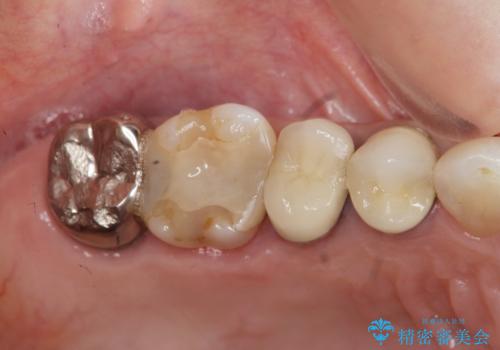

臼歯部メタルフリー再補綴

- 治療してからの年月が経過し、かみにくくなったブリッジ・クラウンを全てやりかえたいと希望され来院されました。

クラウン・ブリッジを作り替えるにあたり虫歯の徹底的な除去・根管治療のやり直しを行い今後やり直しをしなくて済むような環境を整えていきます。

装着して長期間経過したブリッジやクラウンは隙間から細菌が侵入し虫歯が再発してしまっていることがあります。

長期的に問題のないブリッジ・クラウンを作製するため、虫歯をしっかりと除去すること精密な根管治療を行うことが肝要です。